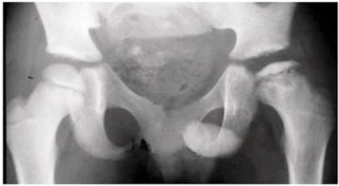

Considere uma criança de 6 anos, com a seguinte imagem radiológica:

Diante do exposto, é correto afirmar que trata-se